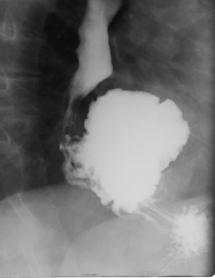

Fig. 26: Hernie traumatica de intestin subtire si colon prin ruptura de diafragm (opacitate intensa, neomogena, pe fondul careia apar o serie de transparente cu aspect de arcuri de cerc situata in baza dreapta: tranzitul baritat confirma diagnosticul)

Fig. 27 – Hernie hiatala prin alunecare

Fig.28: Hernie hiatala prin brahiesofag